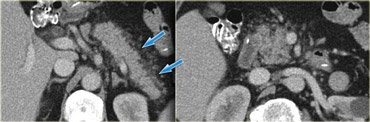

- Exemplos Clínicos (Exames TC):